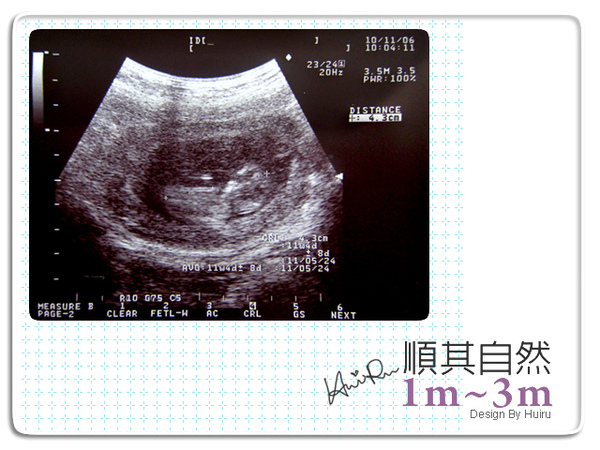

11月6日Sat

今天bb讓我笑了,陳醫師也笑個不停,因為4.3cm的小bb在超音波中超清楚超活潑,右手舉起像個招財貓,一直在頭旁邊上下揮手沒停過,過一下子右小腳彷彿也做起運動一直往前踢踢踢~超搞笑的,可能是因為他太活潑吧,所以超音波抓不到他的動態,這個月真的是明顯大不少。